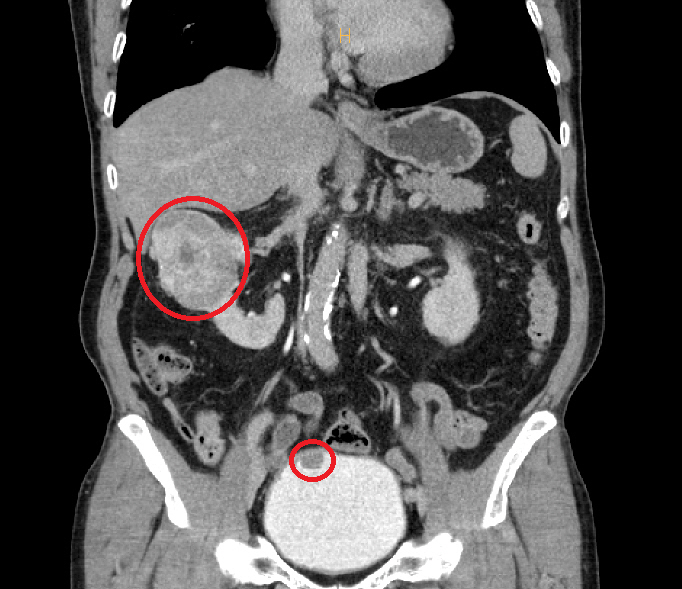

[스포츠조선 장종호 기자] 순천향대학교 부천병원 비뇨의학과 이상욱 교수가 최근 73세 고령 환자의 7㎝ 크기 '신세포암'을 로봇 부분절제술로 제거해 신장 기능을 보존하는 데 성공했다고 12일 밝혔다.

이상욱 교수는 "환자에게서 두 가지 암이 동시에 발견되고 신장 종양 크기도 컸지만, 신장 기능을 지키는 것이 환자의 삶의 질에 매우 중요하다고 판단해 부분절제술을 선택했다"며 "순천향대 부천병원은 다양한 고난도 로봇수술 경험을 바탕으로 환자 맞춤형 수술을 시행해 최적의 치료 결과를 만들고 있다"고 말했다.